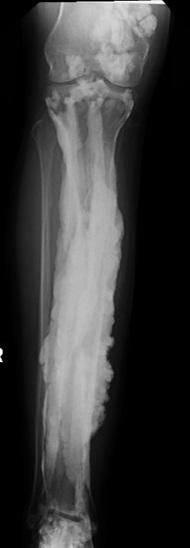

Researchers at the National Institutes of Health worked with 15 patients from around the world to uncover a genetic basis of "dripping candle wax" bone disease. The rare disorder, known as melorheostosis, causes excess bone formation that resembles dripping candle wax on x-rays. The results, appearing in Nature Communications , offer potential treatment targets for this rare disease, provide important clues about bone development, and may lead to insights about fracture healing and osteoporosis.